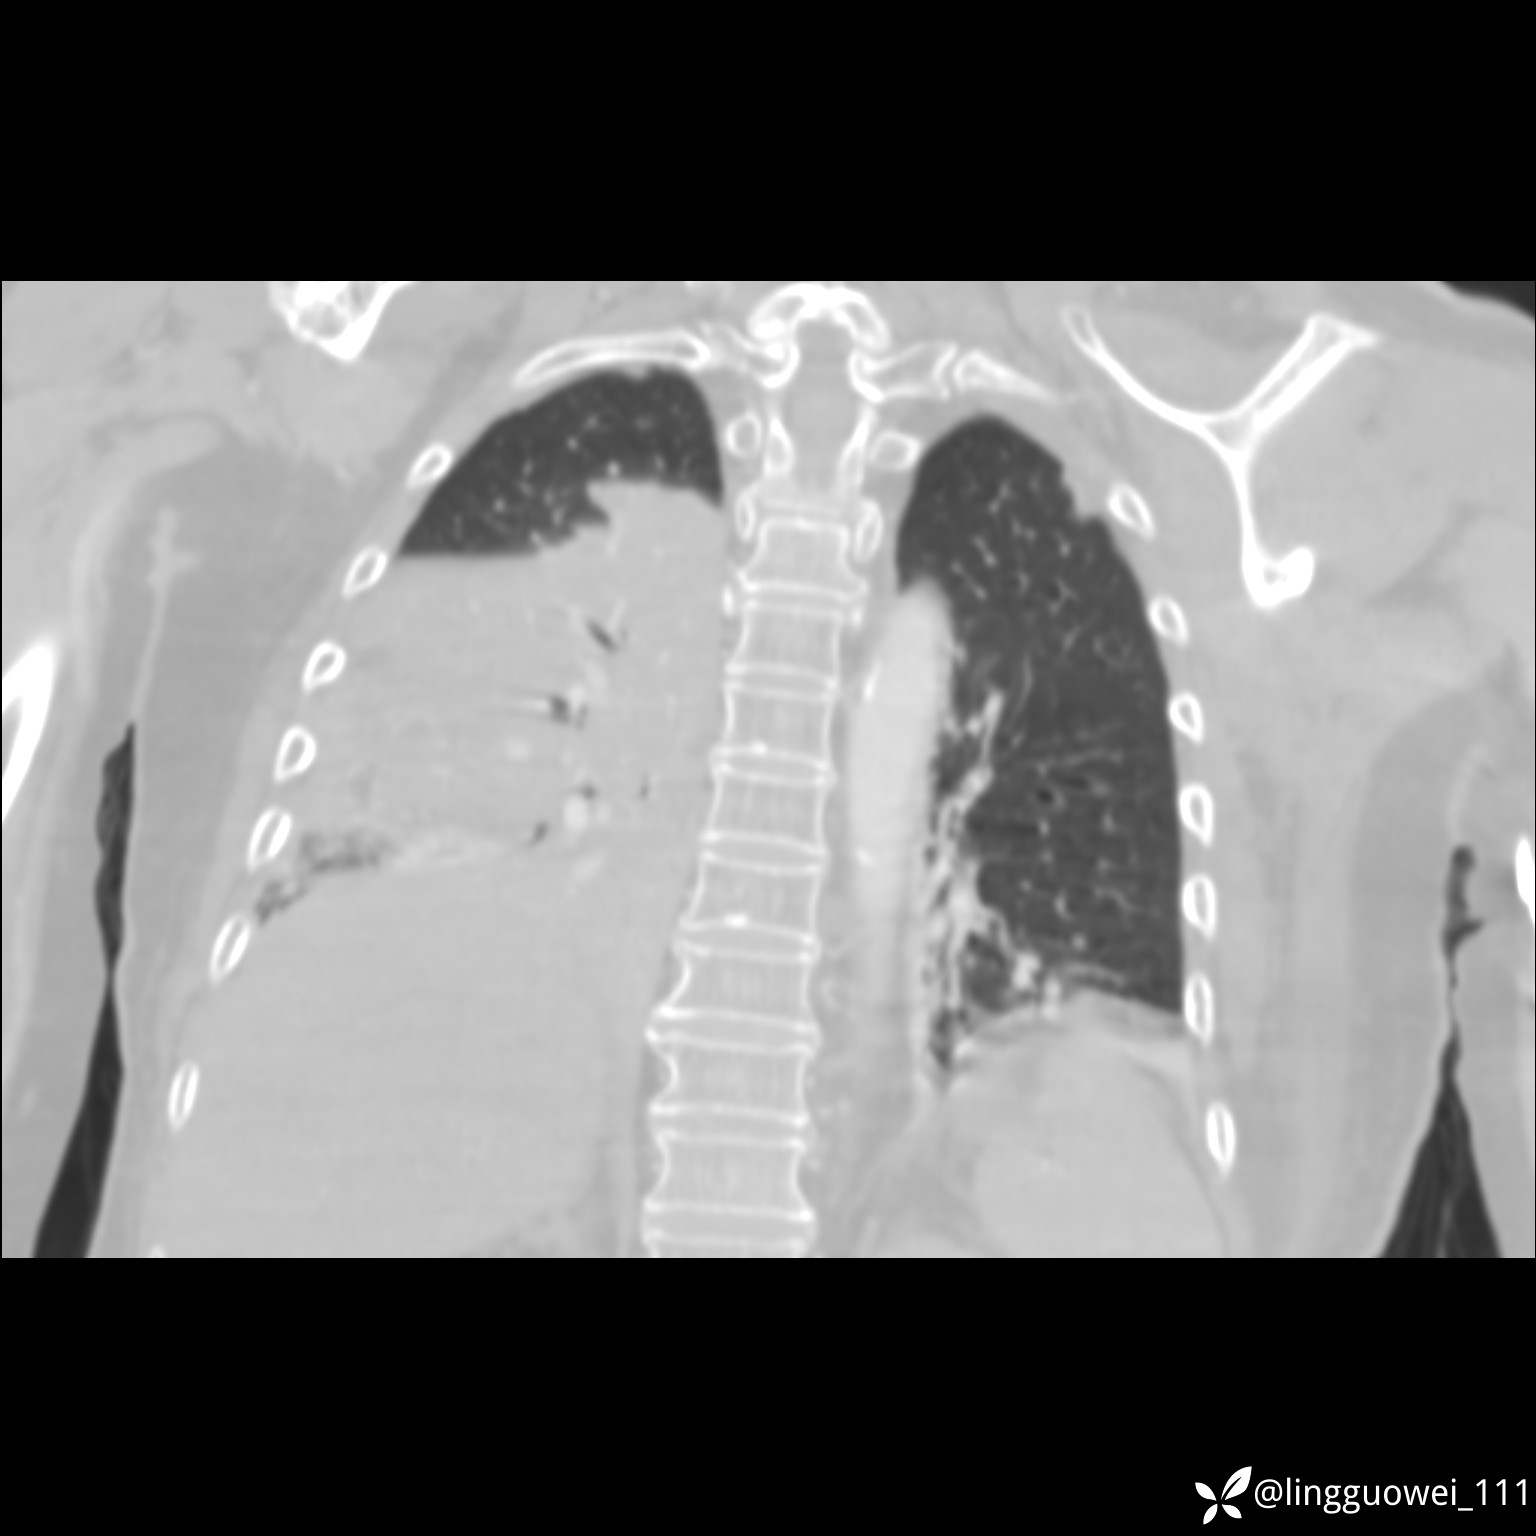

CT平扫:

20小时后,行胸部增强检查,病灶范围较前增大